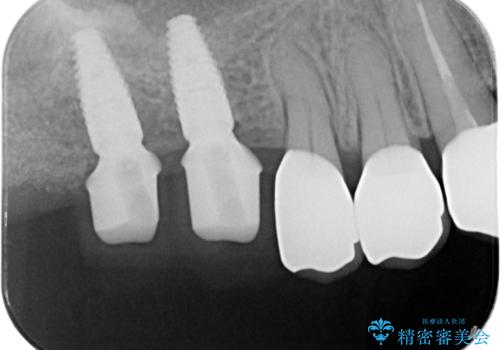

親知らず、ブリッジを抜去・撤去しインプラントを用いた咬合機能回復を行っていくこととしました。

- 123.2万円(インプラント×2・チタンカスタムアバットメント×2・ジルコニアクラウン×4・仮歯×4)費用は治療当時の料金となります